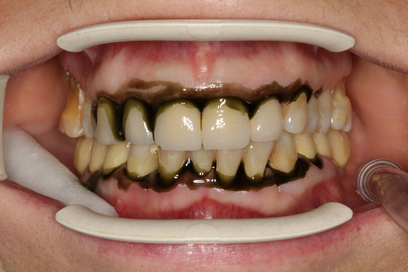

В основной группе 2 на фоне проводимого комплексного лечения с использованием геля «Метрогил-дента» отмечали улучшение как субъективных, так и объективных проявлений заболевания: уменьшались болезненность и кровоточивость десен, галитоз. Через 30 дней после лечения пациенты обеих групп отмечали значительное снижение болезненности, отека и кровоточивости десен, исчезновение неприятного запаха изо рта, некоторое снижение подвижности зубов, появление уверенности при жевании, улучшение общего состояния. При объективном обследовании отмечали уплотнение десневого края за счет уменьшения отека, существенное улучшение гигиенического состояния полости рта, прекращение выделения экссудата из пародонтальных карманов (Рисунок 13).

| до лечения | через 30 дней после лечения |

| Рисунок 13. Динамика состояния тканей пародонта у пациента с ХГП тяжелой степени через 30 дней после комплексного консервативного лечения с местным применением препарата «Метрогил-Дента» . | |